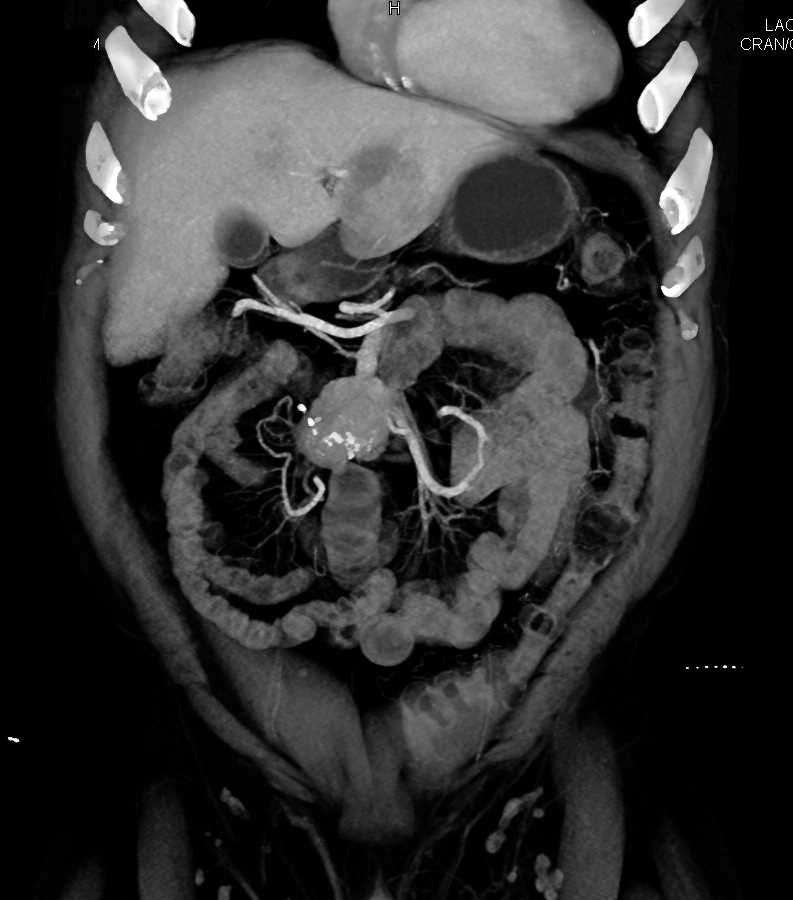

Carcinoid Tumor with Desmoplastic Reaction